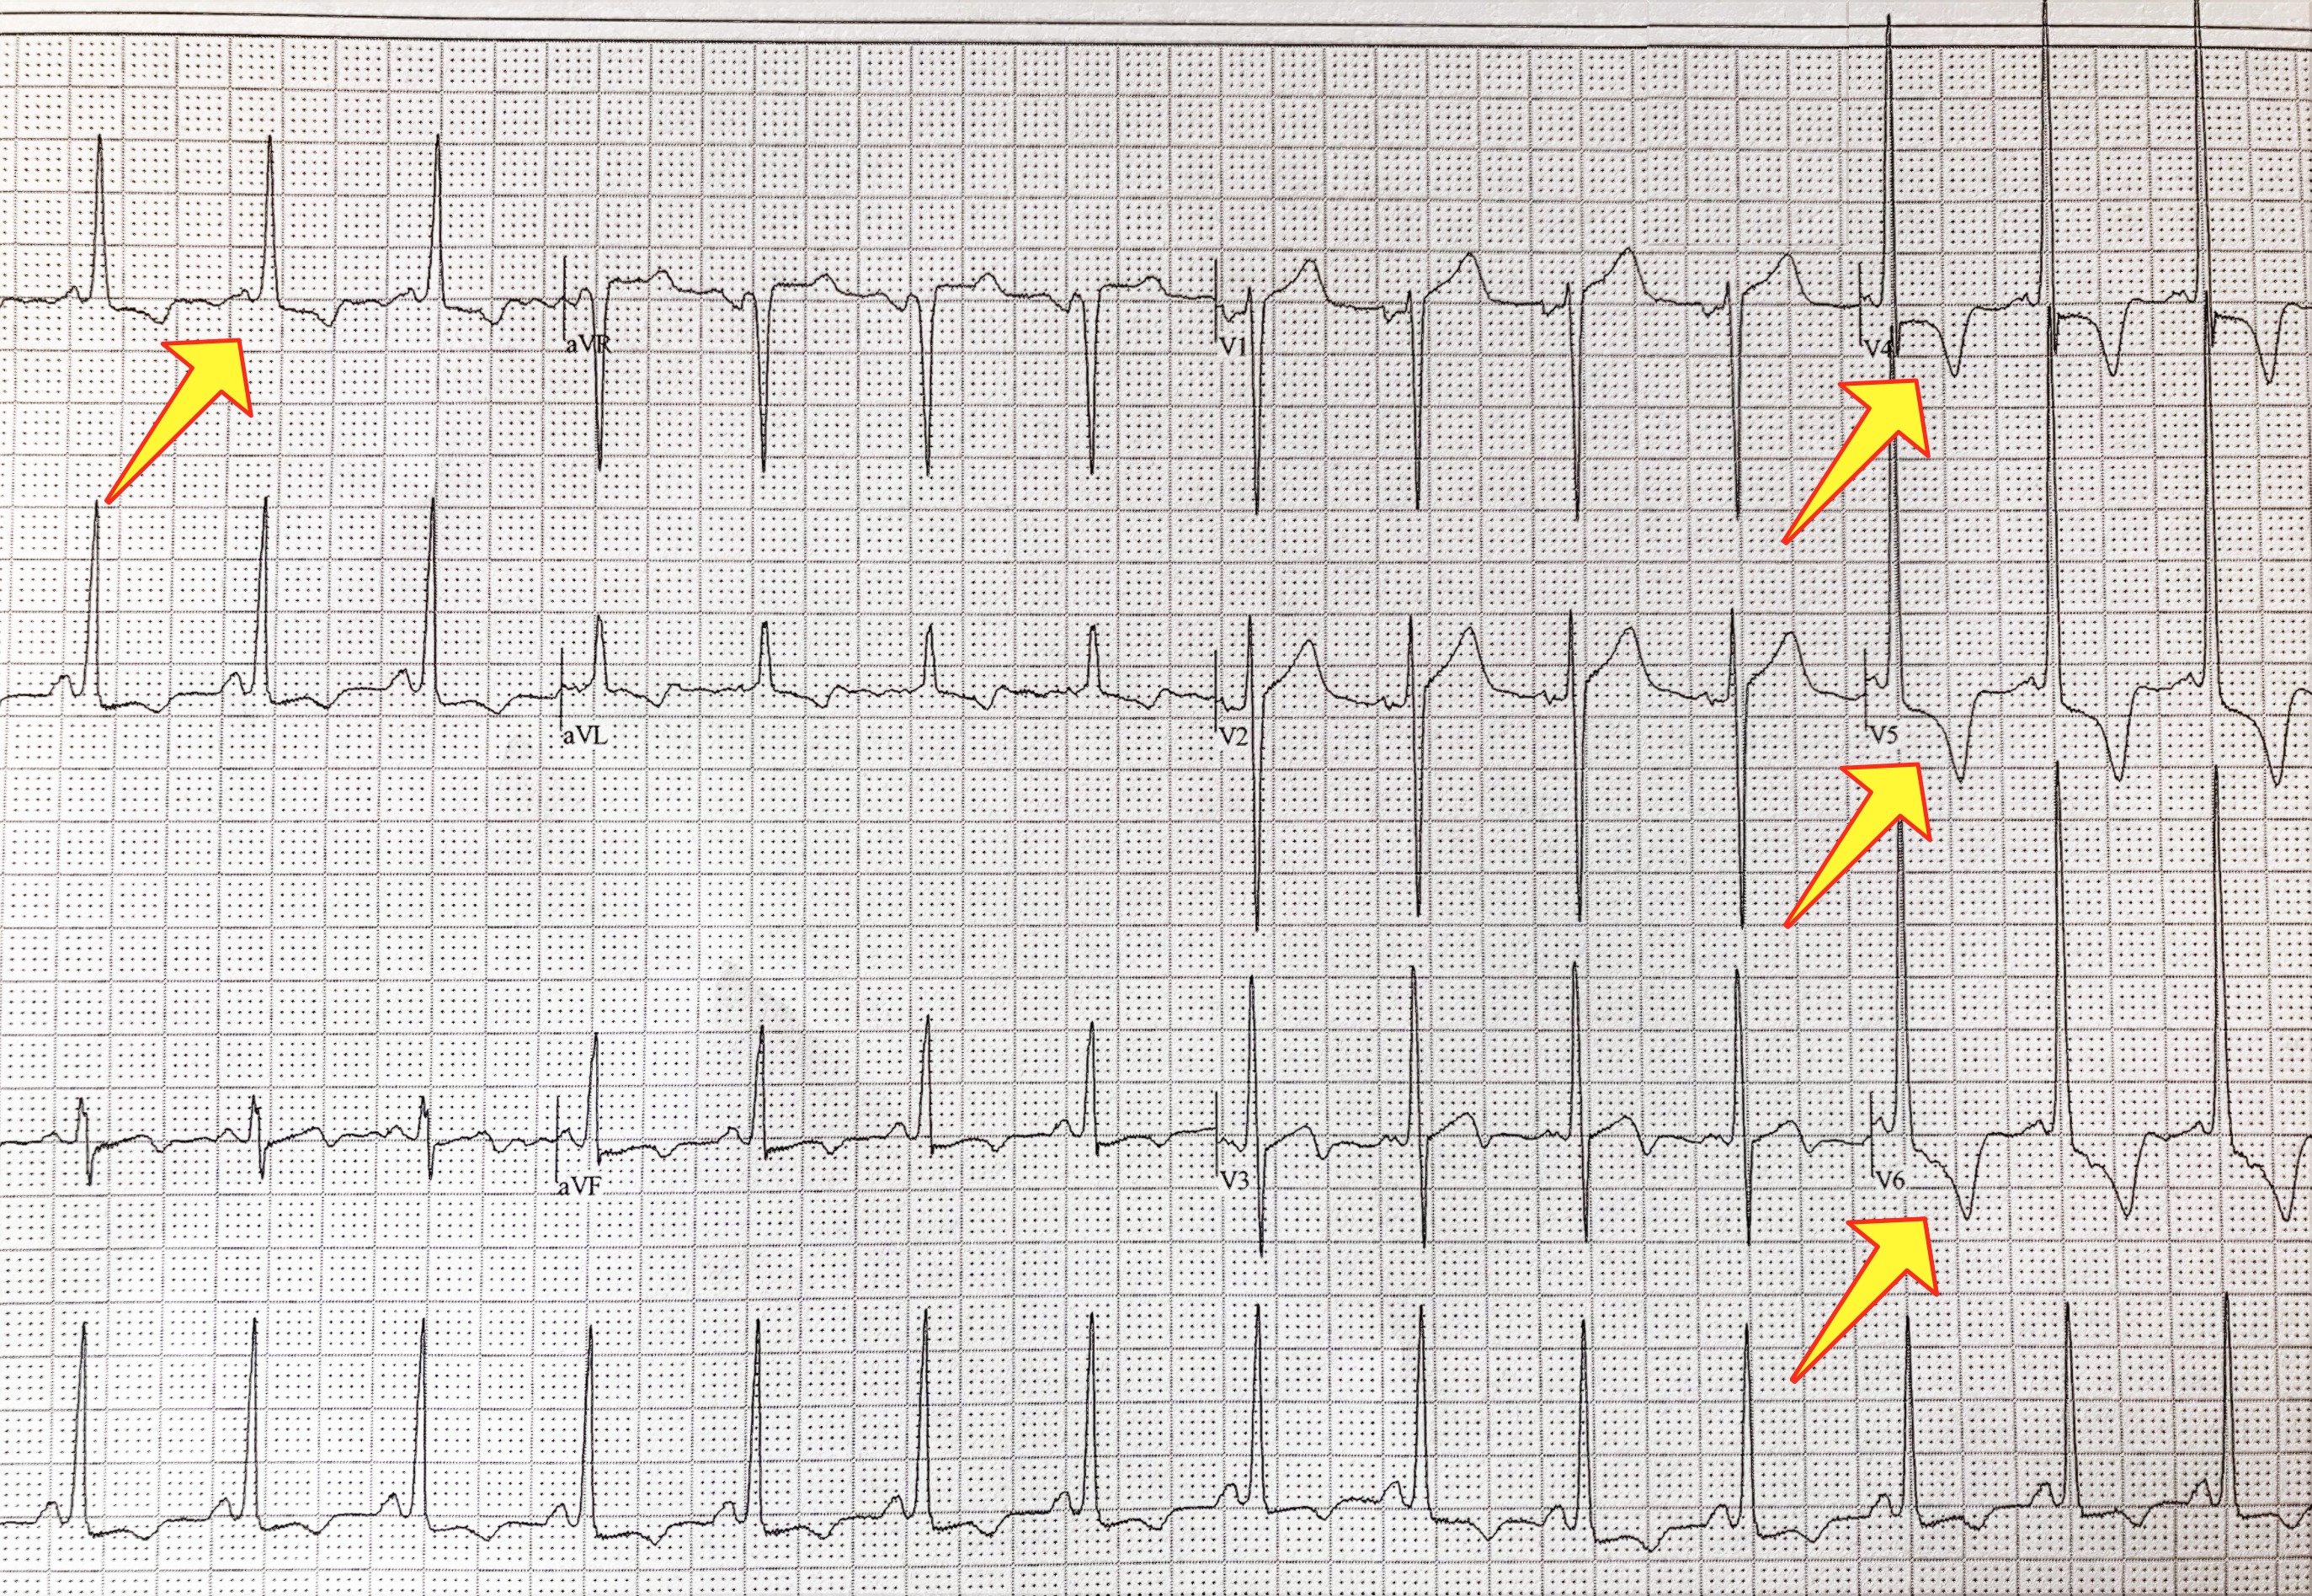

La ecocardiografía es la prueba por excelencia para diagnosticar la cardiomiopatía hipertrófica. El eco puede identificar dónde está el músculo engrasado, medirlo y cuantificar el efecto que este podría estar teniendo sobre el flujo de sangre. Es común que el electrocardiograma de un paciente con MCH salga anormal; esto puede ayudar a entender mejor la condición. El ECG es otra herramienta de detección excelente para HCM. Cuando usted ve a una cardióloga por primera vez, es por eso que se le manda un Eco preliminar. En los últimos años, el MRI cardiaco ha surgido como una de las herramientas más importantes de la proyección de imágenes para el corazón gracias a su capacidad para producir imágenes muy detalladas. Un MRI cardiaco puede ayudar a diagnosticar la MCH con mucha precisión. Puede detectar incluso pequeñas cantidades de músculo grueso que podrían no ser detectadas en la ecocardiografía.